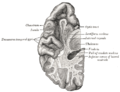

صور اضافية